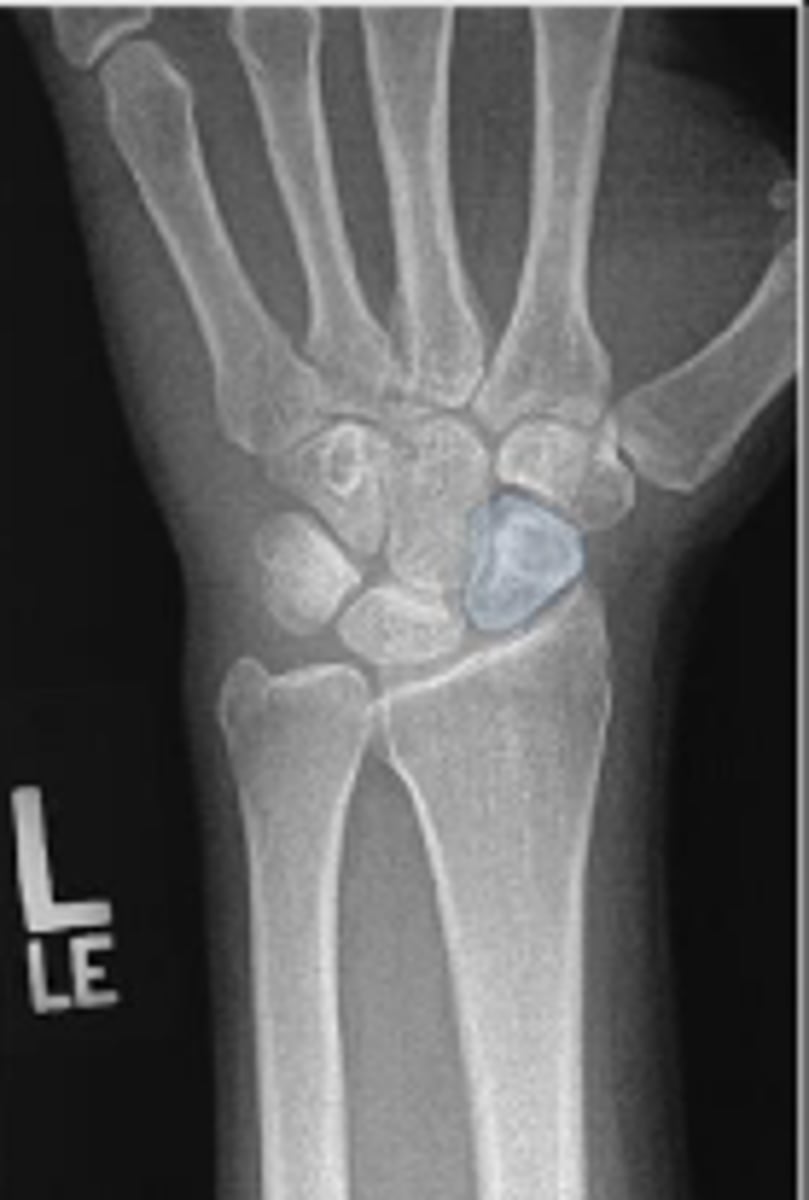

Left lunate

What is outlined?